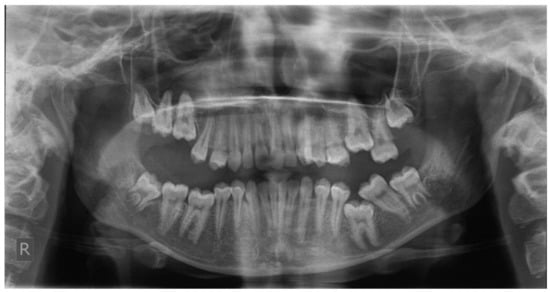

Figure 6.

Left photo of the same female patient depicted in Figure 5.

Open bite is present at the right posterior segment due to the impaction of the upper and lower left first molars.

Figure 5 and Figure 6 present a PFE case of a 17-year-old female patient referred to the Orthodontic Clinic of the Dental School of the National and Kapodistrian University of Athens, Greece. Clinical examination showed a posterior open bite on the right segment, as well as infraoccluded left upper and lower first molars. The patient’s orthopantomography shows no visible PDL of the right upper and lower first molars or the teeth distally related to them.